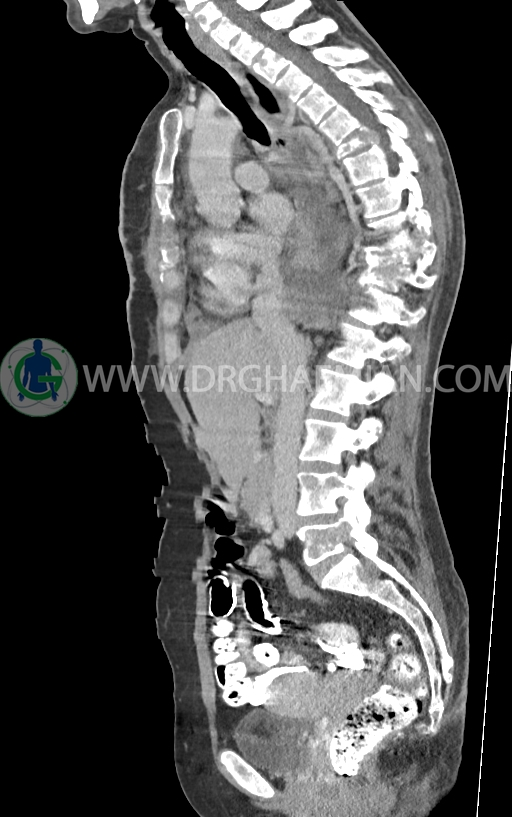

در سی تی اسکن اسپیرال ریه و مدیاستن -شکم و لگن با کنتراست خوراکی و وریدی (مولتی دیدکتور 16 با مقاطع ظریف و بازسازی های ساژیتال و کرونال) :

–ضایعات استخوانی لیتیک فراوان منتشر در تمامی طول ستون مهره و لگن رویت شدند که مطرح کننده متاستاز استخوانی می باشند.

–شکستگی پاتولوژیک در مهره های T6 , T10 , T11

–کیفوز موضعی در Level T10 , T11 در ستون مهره

–رتروپالشن شکستگی مهره T10 همراه با ایجاد تنگی کانال نخاعی